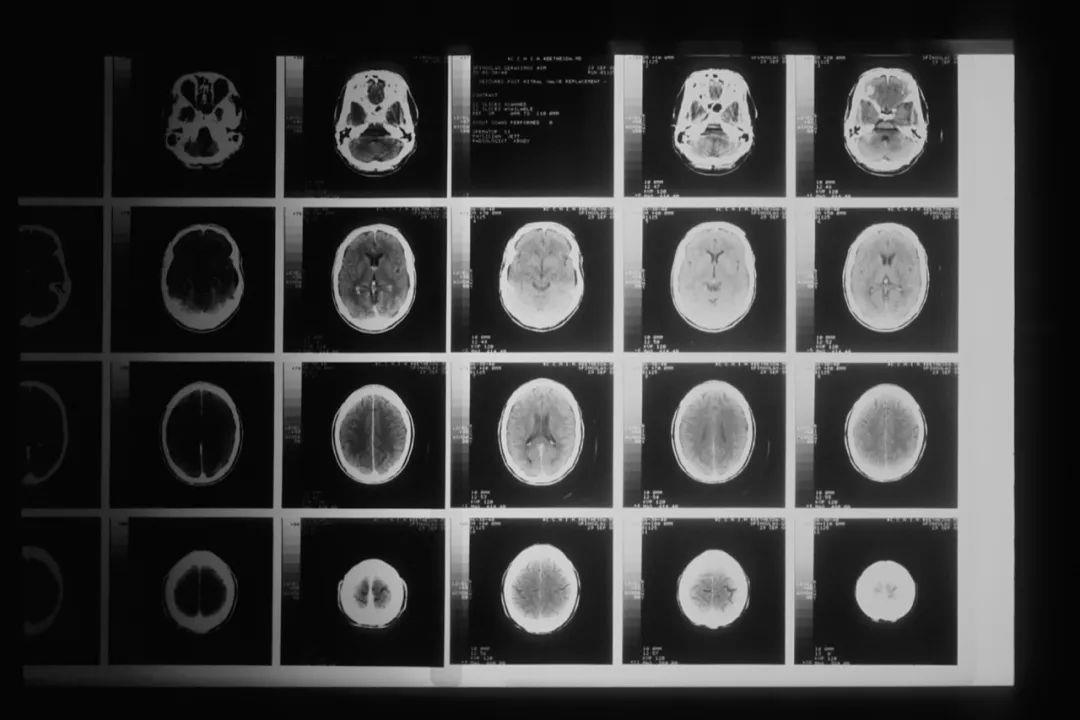

最新研究!新人工智能模型可预测脑胶质瘤治疗效果

脑胶质瘤是指起源于脑神经胶质细胞的肿瘤,是成年人最常见的原发性颅内肿瘤。我国脑胶质瘤年发病率为每10 万人中有5~8例,5 年病死率在全身肿瘤中仅次于胰腺癌和肺癌。但脑胶质瘤发病的内在机制尚不明了,目前确定的两个危险因素是:暴露于高剂量电离辐射和与罕见综合征相关的高外显率基因遗传突变。

脑胶质瘤的标准疗法以手术切除为主,结合放射治疗与使用化学药物替莫唑胺(TMZ)进行综合治疗。手术可以缓解临床症状,延长生存期,但往往只可延长患者约三个月的寿命,因为几乎所有患者都会面对脑胶质瘤复发的问题。医学界当前仍未厘清这套标准疗法为什么会促使脑胶质瘤恶化。

为了解开这个谜团,由香港科技大学生命科学部和化学及生物工程学系夏利莱夫人、生命科学副教授王吉光领导的研究团队,全面分析了544位脑胶质瘤患者的肿瘤分子样本和临床数据,其中包括182名东亚患者,以辨识不同种类脑胶质瘤演化的基因组和转录组预测因子。相关成果发表在《科学·转化医学》上。

透过大数据分析,研究团队发现一些与TMZ抗药性及脑胶质瘤快速恶化相关的早期预测因子,比如患者在初次诊断时已发现某个基因的数量增多,或某个基因被过度激发,或某个基因缺失,他们后期肿瘤急剧恶化的机率会更高。发现这些脑胶质瘤复发的早期预测因子,将有助开发针对这种恶性肿瘤的精准治疗方案,为患者带来裨益。

图源:National Cancer Institute